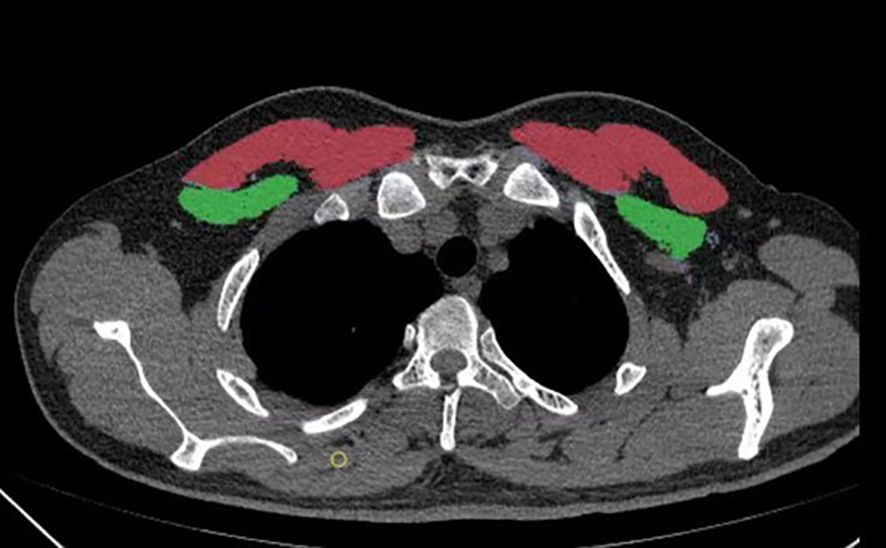

A six-row spiral CT scanner (SOMATOM Emotion 6; Siemens, Munich, Germany) was used for chest CT scans. The scanning parameters included a tube voltage of 120 kV, automatic tube current adjustment, and a layer thickness of 0.625–2 mm. The CT images were analyzed with 3D Slicer, an open-source software application. The T4 level was defined as a middle slice of the fourth thoracic vertebra. The pectoralis major and minor muscles were manually segmented bilaterally. The bilateral pectoralis muscle area (PMA) was automatically calculated by summing the pixel attenuation within a threshold range of -29 to +150 HU for skeletal muscle (Figure 2). The pectoralis muscle index (PMI) was derived by dividing the PMA by the square of the height (cm2/m2). To assess inter-rater reliability, a second physician, blinded to the initial results, performed the measurements on a random sample of 100 subjects. Both measurements were performed by professionally trained physicians.

CT scan cross-section of the thorax showing lung fields. Areas highlighted in red and green on both sides represent specific anatomical or pathological regions. Bone structures appear in white.

Figure 2. A method for determining pectoralis muscle area (PMA) by computed tomography (CT) with open-source software of 3D Slicer. a Horizontal plane of the T4 level; the pectoralis major is red, and the pectoralis minor is green.